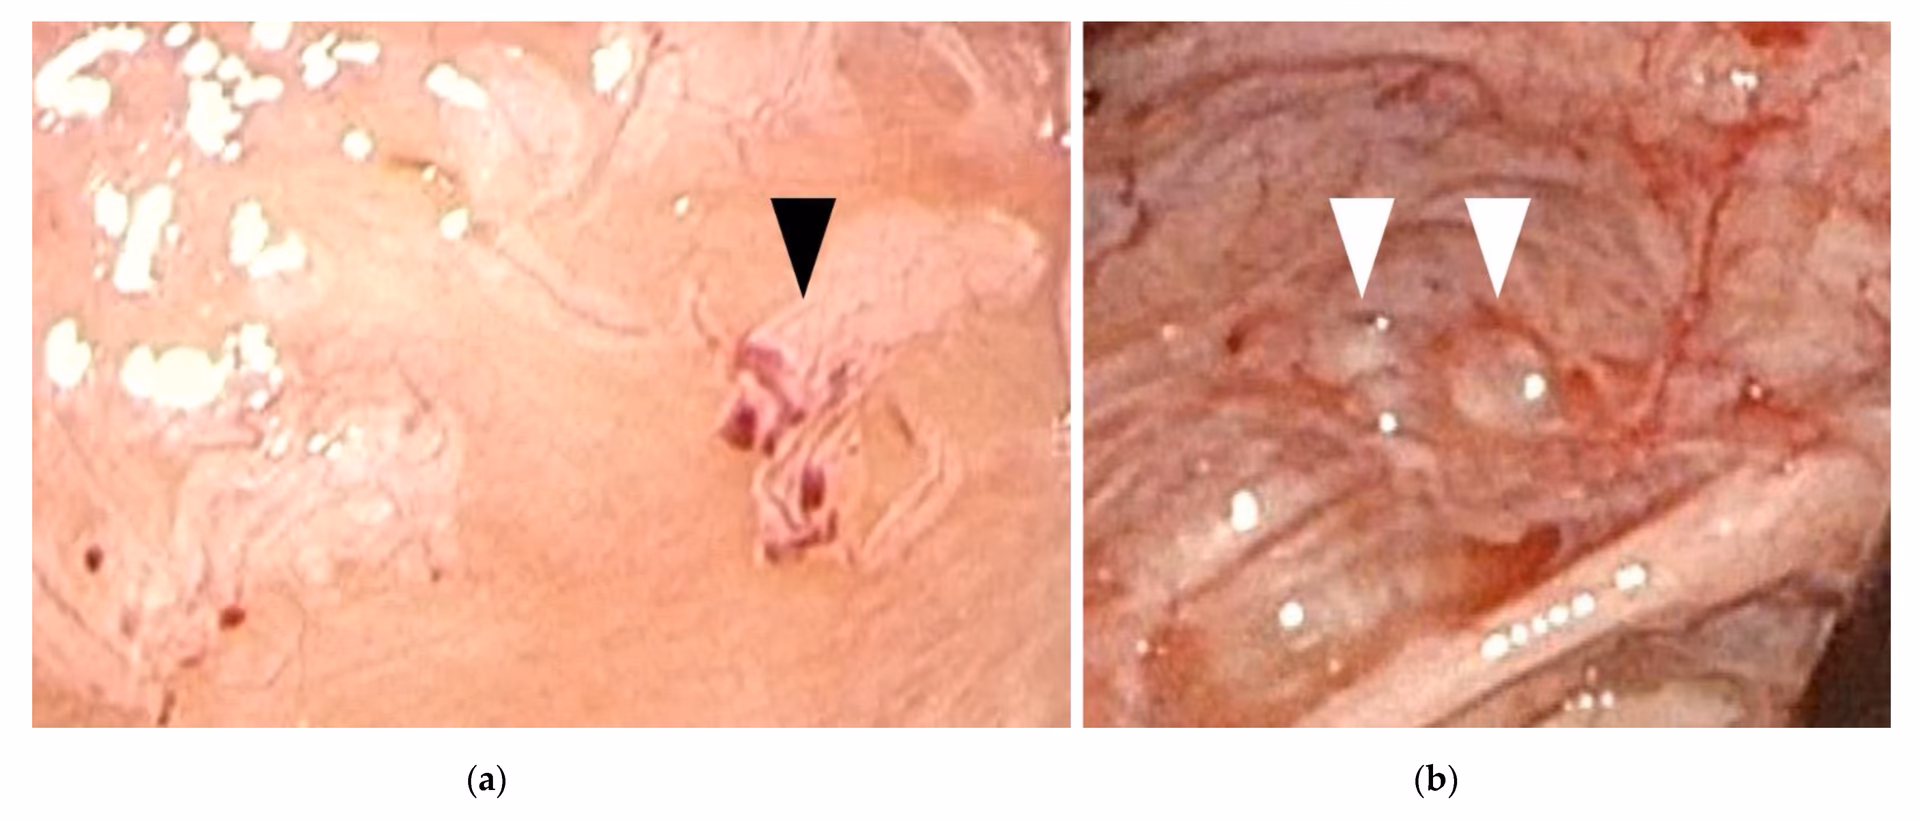

Diagnosen starter med en grundig samtale om dine symptomer og en gynækologisk undersøgelse. En ultralydsscanning kan nogle gange vise endometriose-cyster på æggestokkene, men den kan ikke se de flade læsioner på bughinden. Den eneste sikre måde at stille diagnosen på er ved en kikkertoperation (laparoskopi), hvor en kirurg kan se direkte ind i bughulen. Læger vil dog ofte starte behandling baseret på en stærk mistanke ud fra symptomerne for at undgå en operation.